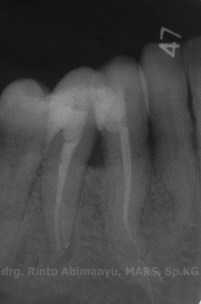

Radiografis gigi 43 selesai perawatan

Alhamdulillaaaah… saluran yang sedikit meliuk itu berhasil diisi dengan baik… 🙂